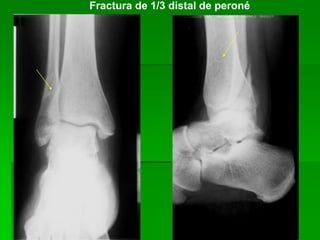

Fractura de 1/3 distal de peroné

Fractura en 1/3 distal de peroné y tibia